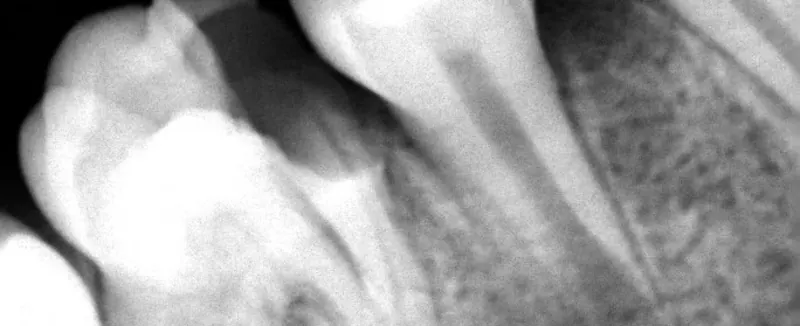

Extracción de terceros molares, colocación de implantes y cirugías con enfoque conservador.

• Especialista en Cirugía Bucal

• Experta en extracción de muelas del juicio e implantología